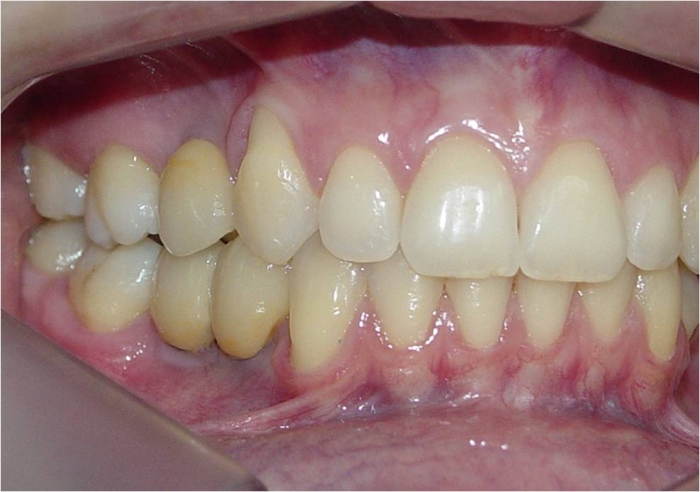

Dentes de porcelana instalados sobre implantes